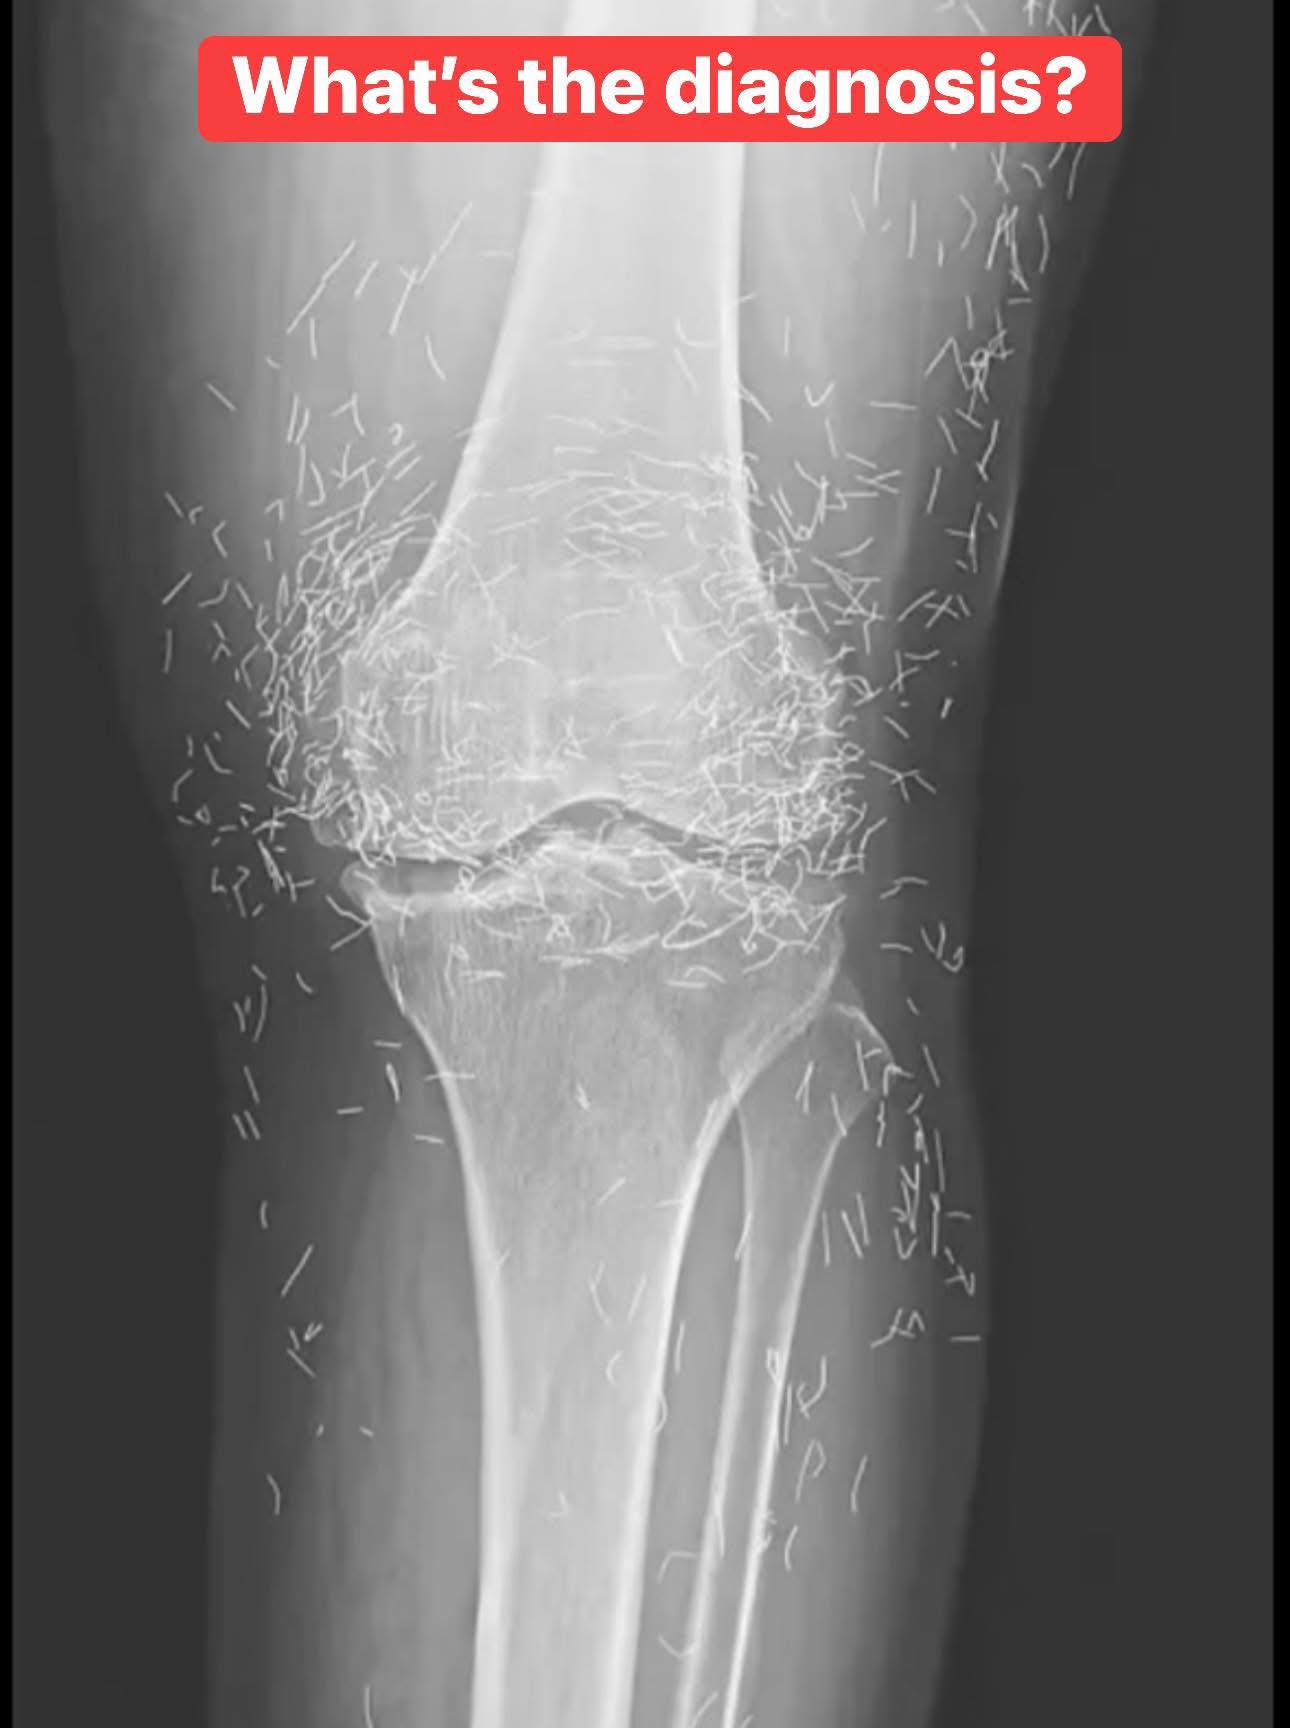

Doctors find “gold mine” in woman’s knees

When a 65-year-old South Korean woman went in for knee pain, doctors weren’t expecting to strike gold. But that’s exactly what they found. Unwanted stomach issues Living with osteoarthritis can…[...]